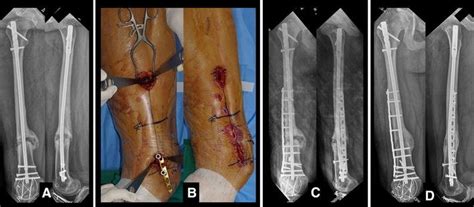

A femoral neck fracture is associated with high morbidity and mortality. Nonunion is permanent failure of healing following a broken bone unless intervention (such as surgery) is performed. High rate of fracture union if appropriate treatment is selected based on patient age and fracture pattern.

Prolonged immobility following the fracture may increase the risk of the following. In spite of advances in treatment, femoral neck fractures are complicated fractures with a relatively high incidence of nonunion. A fractured neck of the femur is always an emergency and reduction and fixation must be done in 24. Indications for conservative treatment of fractures of the shaft of the. Neck of femur fracture carries significant mortality with a tenth of patients dying in the first month and a third within the first year following the injury.3. What is a fracture nonunion? Valgus osteotomy of the femur is a suitable procedure for treatment of femoral neck nonunion in young patients, since it is easy to perform and yields relatively good results. These complications of fractures and their treatment are inevitable in some patients, but it is the concepts of slow union delayed union, and nonunion are based primarily on the state of activity and rate of progression of the repair process. For this prolonged period resulted in severe shortening and osteoporosis. Femoral neck fracture is a type of hip fracture common in elderly, osteoporotic women. What everyone with a non union fracture needs to know. Because they are easily applied, external fixators are often put on when a patient. Nail dynamization for delayed union and nonunion in femur and tibia fractures. Since this initial description by heng et al. Proximal femoral fractures are a very common disease which affect elderly patients after low energy trauma, but can also affect the young population as a consequence of high energy keywords: For example, if you are your healthcare provider might recommend nonsurgical treatment for a very young child, or for. Most femur fractures are fixed within 24 to 48 hours.